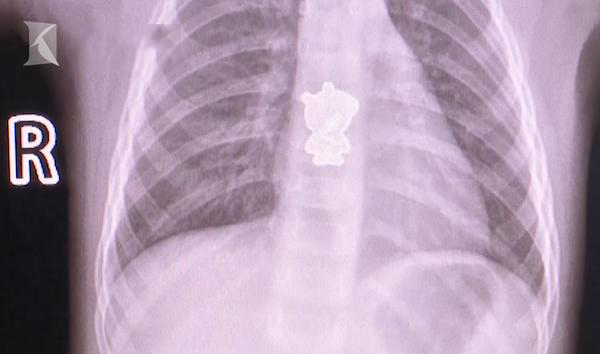

Bé gái ho ra máu vì nuốt phải hình dán heo Peppa

Sau khi chụp CT, bác sĩ và gia đình tá hỏa phát hiện một vật thể lạ có hình dáng "heo Peppa" bên trong thực quản của cô bé 2 tuổi.